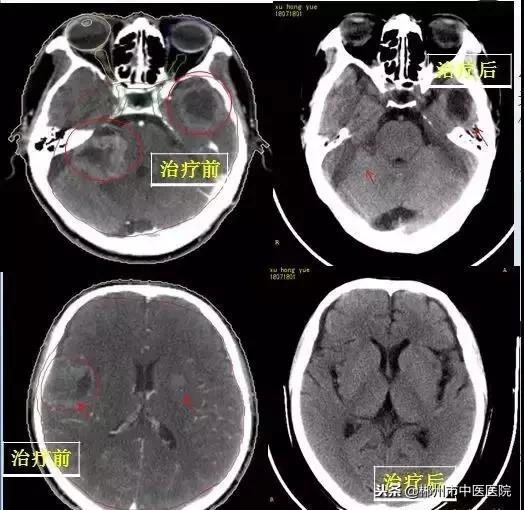

患者谢某,男,48岁,因“头晕、头痛2月,发现颅内肺部占位1月”,病检报告示:小细胞肺鳞癌。头颅核磁共振示:右侧桥小脑角区、小脑蚓部、右额叶、左颞叶、左侧基底节区及左侧岛叶后部多发占位病变,多考虑转移瘤。患者于2018年7月16日在我科行陀螺刀治疗,患者治疗后三个月的对比图如下: